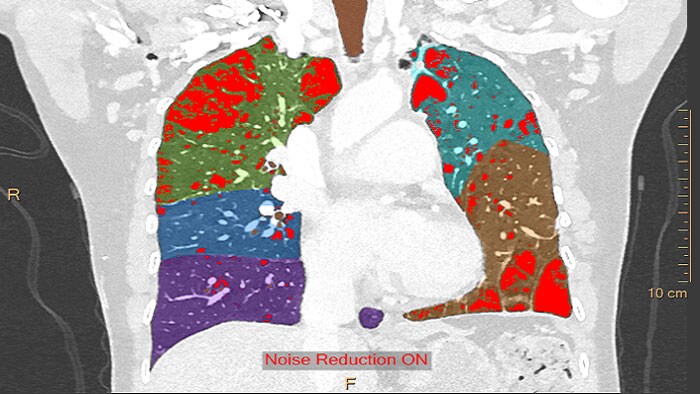

Análise das artérias pulmonares por CT

Um conjunto completo de ferramentas semiautomáticas e manuais para visualizar os pulmões (individualmente ou em conjunto) e rever os resultados, assim como marcar e assinalar qualquer resultado de embolia pulmonar.